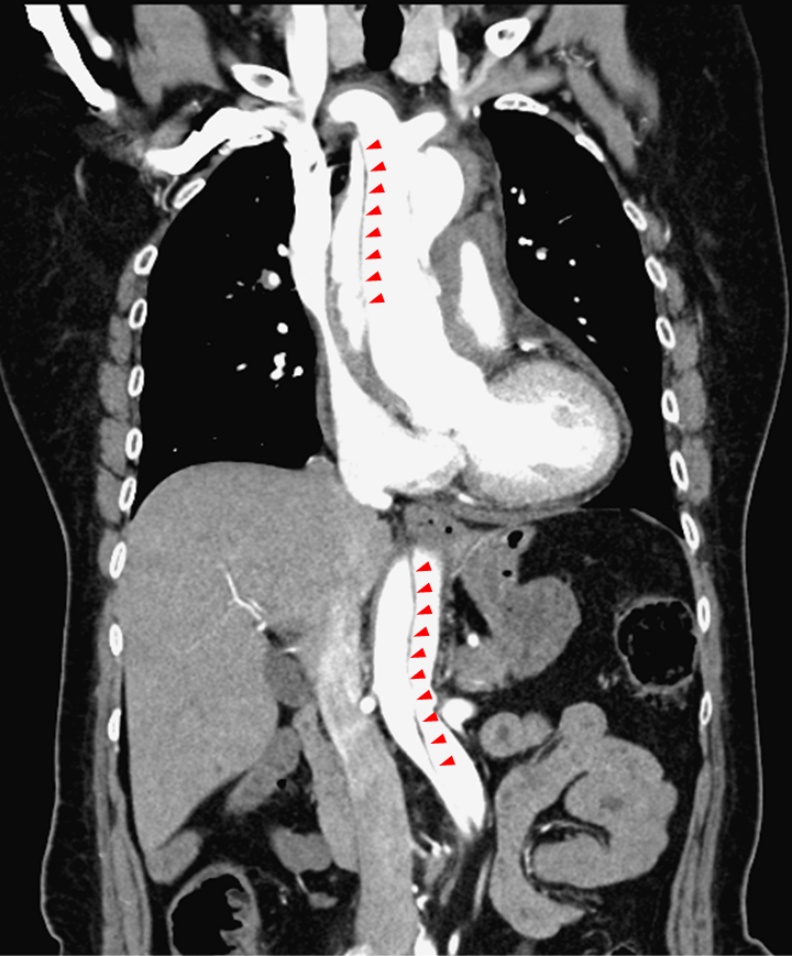

台北市立聯合醫院陽明院區心臟血管內科主治醫師李穎灝指出,主動脈是身體最大的動脈,心臟打出血液後,透過主動脈將血液輸送全身各處。主動脈有三層結構,當血管壁經長年血流沖刷及慢性病摧殘後,內層可能形成裂縫,血液流入內層與中層之間,形成「假腔」,擠壓到「真腔」(正常的血流途徑),導致血液供應受阻。

狀如拐杖的主動脈,上行部分稱為升主動脈,轉彎部分是主動脈弓,下行部分則為降主動脈。剝離位置影響到升主動脈的屬於A型,未影響升主動脈的則為B型。A型容易產心臟相關的併發症,死亡率較B型高,若未緊急手術,發病48小時內致死率可高達50%。